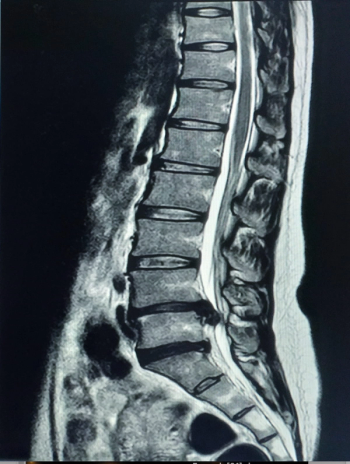

The MSKai software provides AI-powered segmentation, labeling, and measurement tools for assessment of T2-weighted MRIs of the lumbar spine.